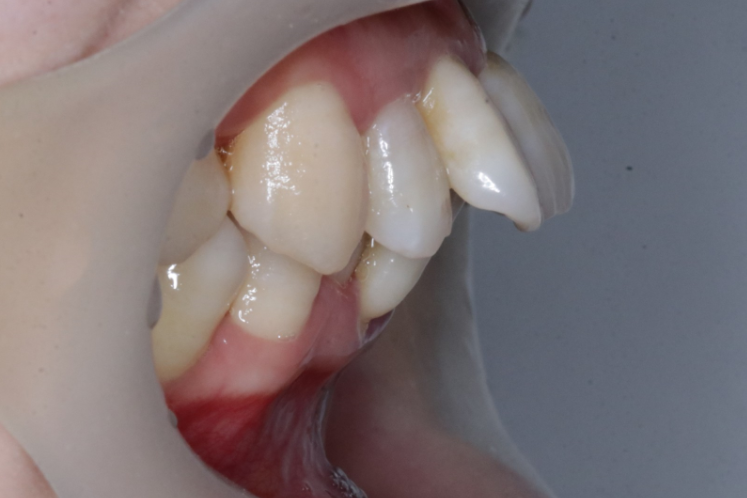

乳牙早失导致拥挤

间隙保持器为“新牙”萌出保留空间

2、阻断矫治。当错颌畸形发生的早期,通过简单的方法进行早期矫治,阻断错颌畸形的发展,并引导面部向正常发育方向发展,常称阻断矫治。如早期前牙拥挤(牙弓缩窄等)使用扩弓矫治器矫治,早期牙源性前牙反合使用简单合垫舌簧矫正器矫治。

治疗前                        治疗后

术前→术后